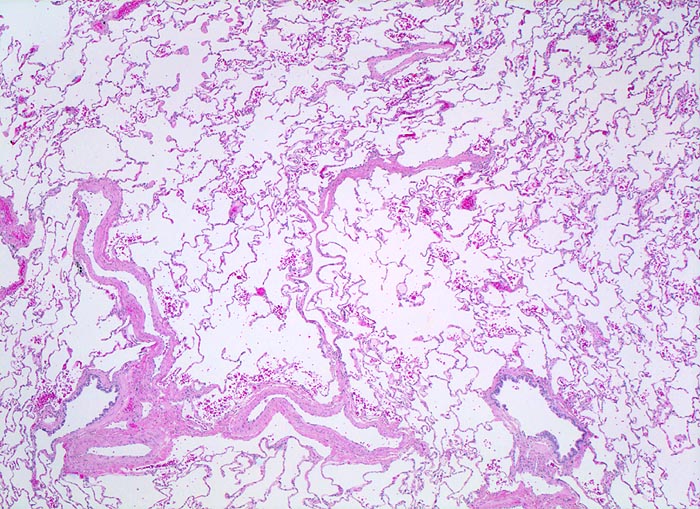

Normalbefund